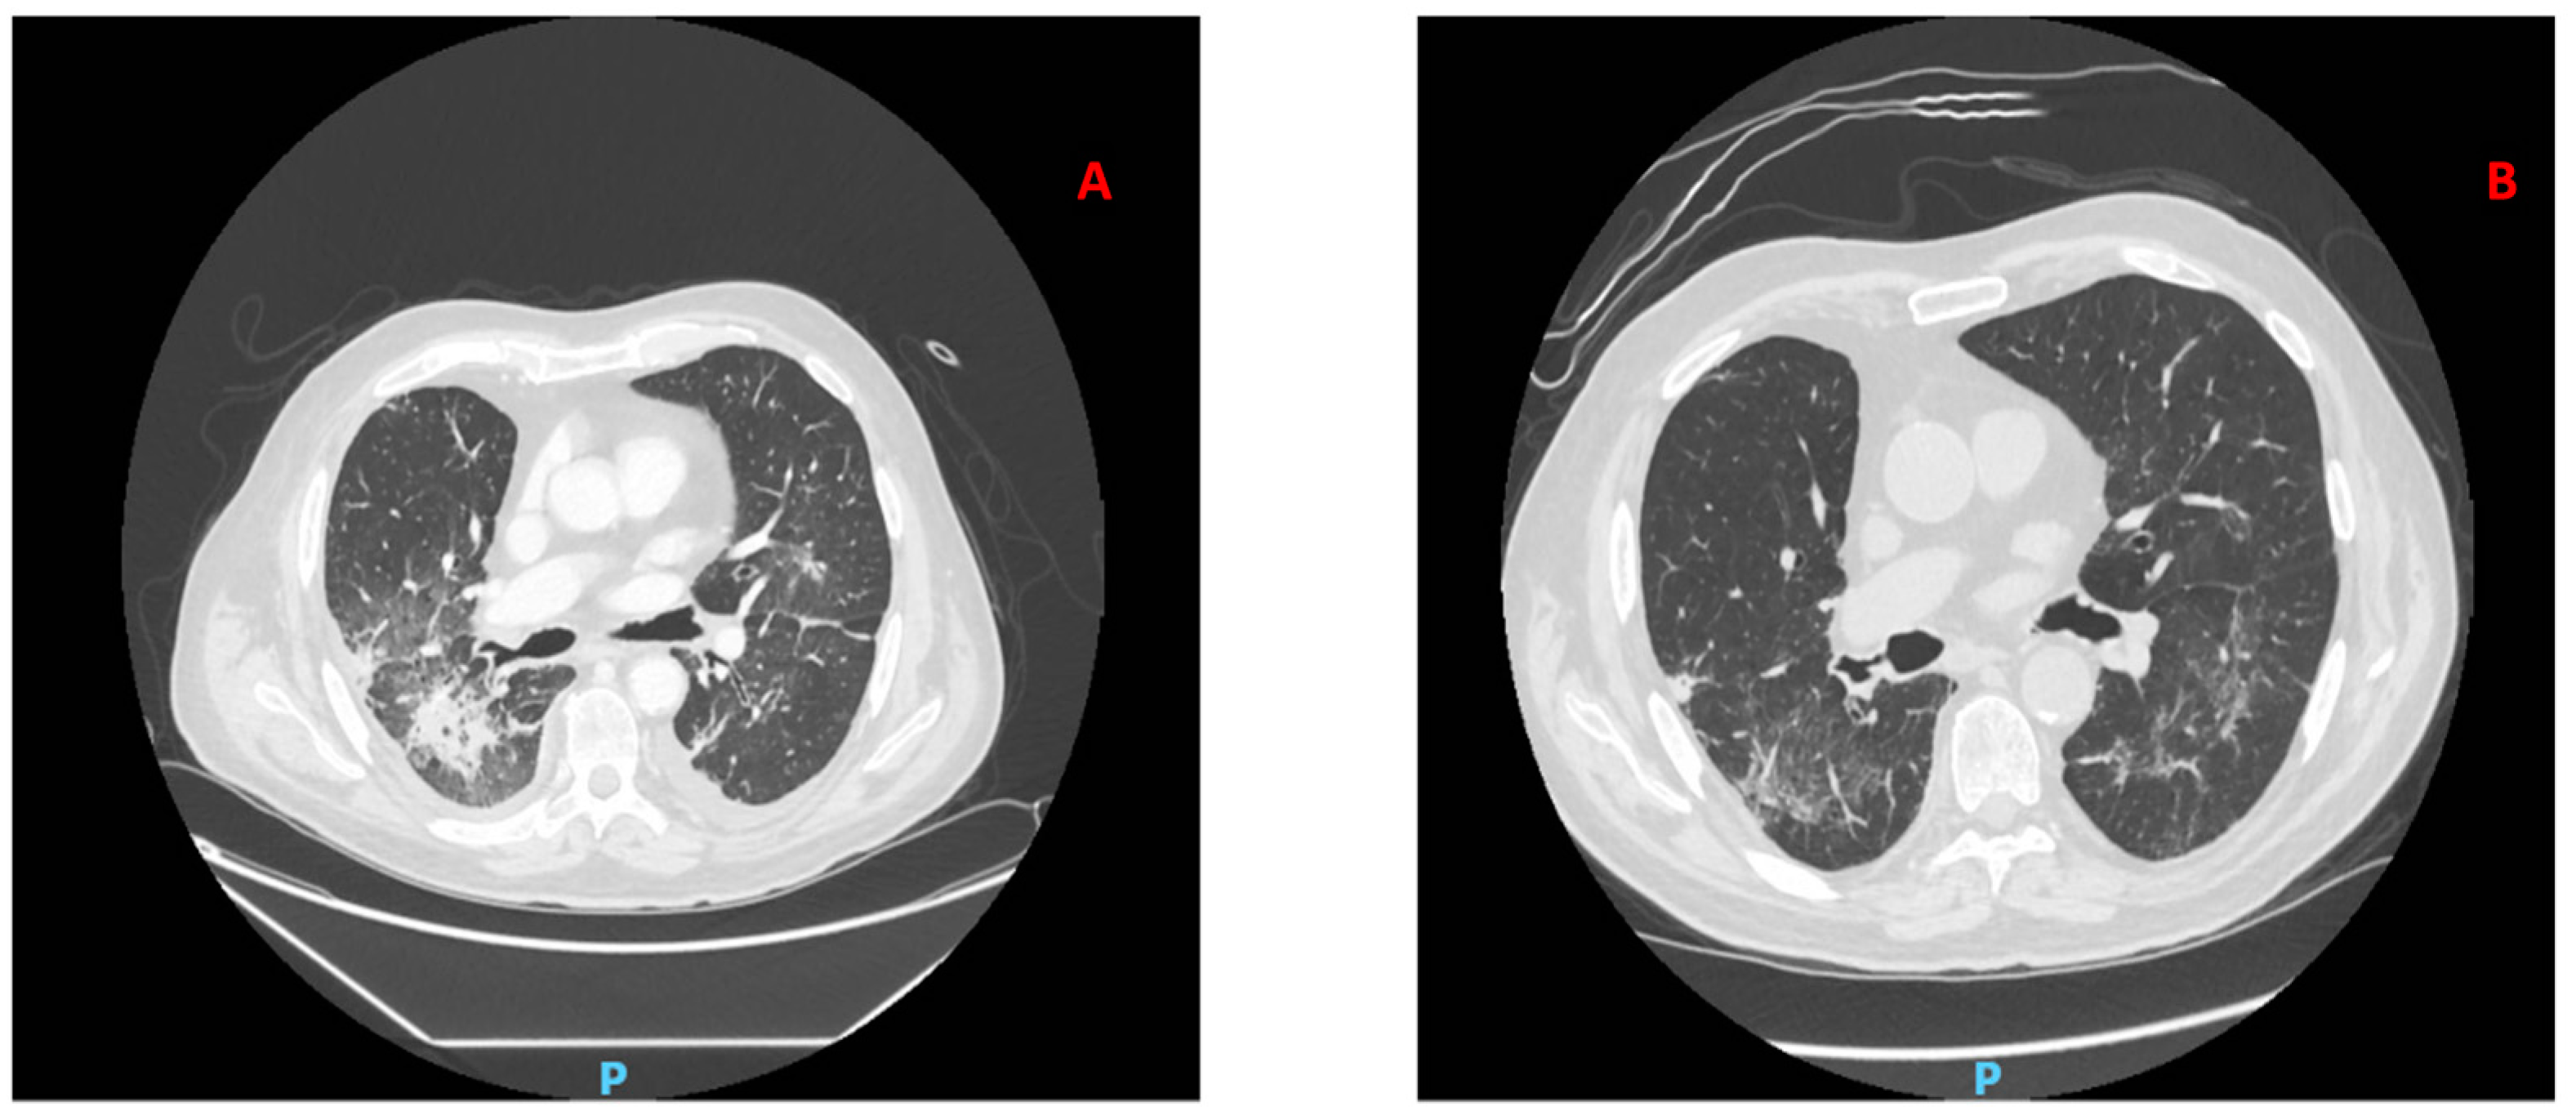

2. Case Report